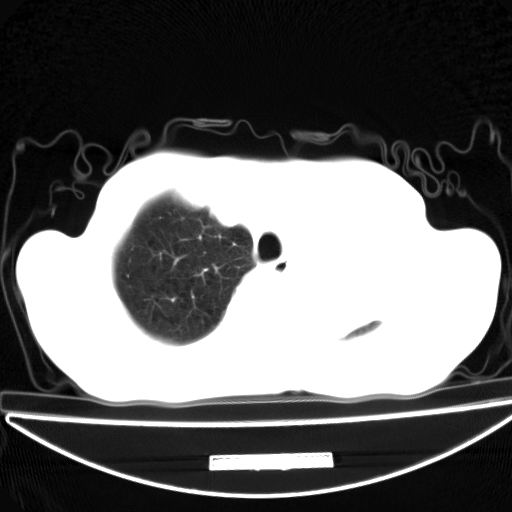

以下是引用杀毒软件在2009-4-28 17:58:00的发言:[br]考虑----左肺慢性肺脓肿形成继发上叶含气不良---抗炎后复查---待排肿瘤所致[br][br][本贴已被 杀毒软件 于 2009-4-28 18:01:26 修改过]